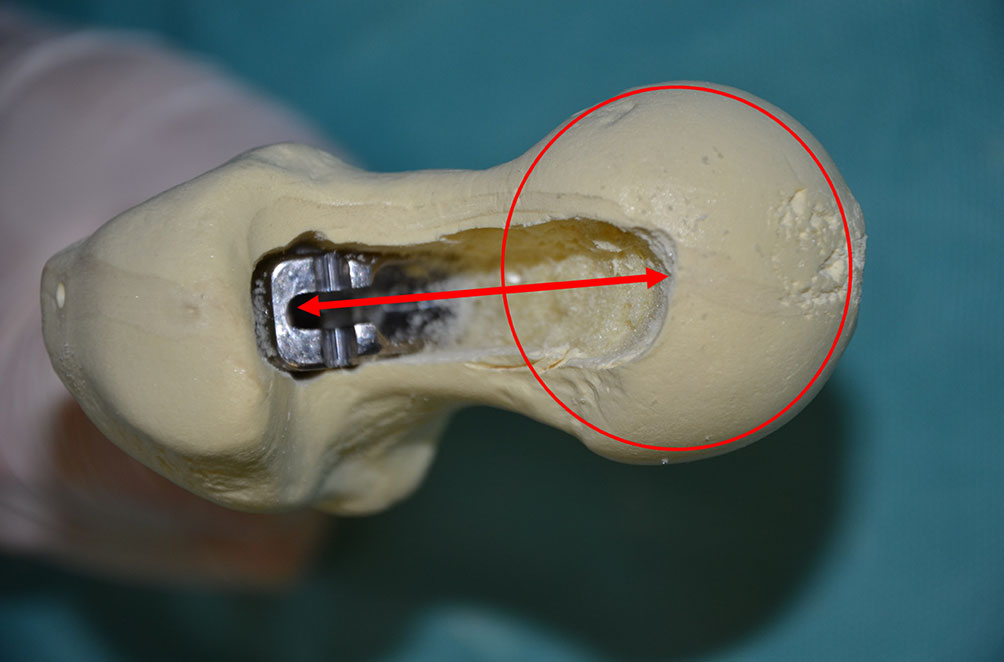

圆形股骨矩锉(貌似洛阳铲)开槽后,用股骨矩刮匙插入股骨髓腔,刮除股骨近端髓腔内侧的松质骨,以确保假体在髓腔内获得良好的皮质骨接触,然后用型号递进的绞刀或髓腔锉依此扩髓,髓腔锉填充满意且转子尖与髓腔锉肩部之间的距离约1.5cm为最佳,将髓腔锉留在髓腔内。